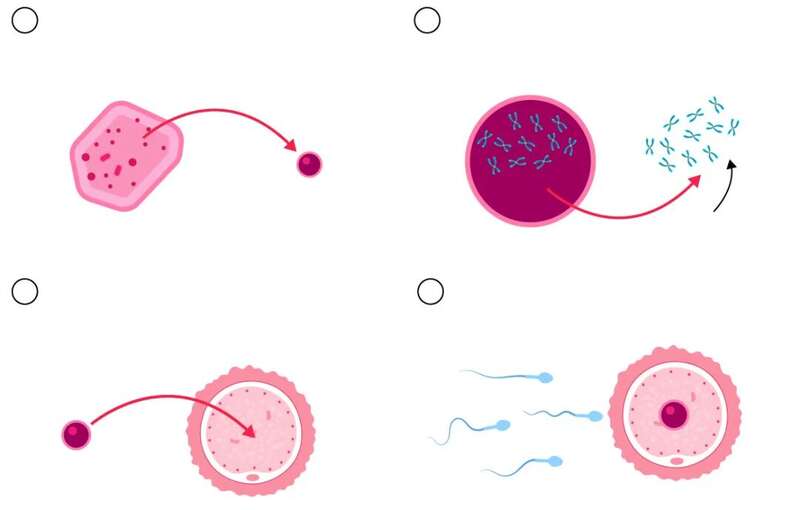

第一步,他们从一位志愿者的皮肤细胞中取出细胞核。里面装着全部遗传密码,也就是你全身上下的“蓝图”。

第二步,把这个细胞核塞进一个“空壳”卵子里。这个卵子原本的遗传物质已经被清空,就像清空内存准备重装系统。

但问题随之来了:皮肤细胞有46条染色体,卵子却只能有23条。那怎么减半?

于是,科学家开发了一种新型细胞处理法,给它起了个酷酷的名字——“mitomeiosis”(米分裂),结合了有丝分裂(mitosis)和减数分裂(meiosis)的特征。

你得让一个没见过世面的皮肤细胞,突然学会做卵子的工作:排卵、配对、染色体交叉、重组……而它的学习过程,大概就是“抓阄扔染色体”。

学家发现,这些“重编程卵子”会随机扔掉染色体,搞得有些胚胎是“24条”、有些“22条”,还有一些把两条21号染色体留了下来——大概率就是以后无法发育,或者导致严重基因异常的孩子。